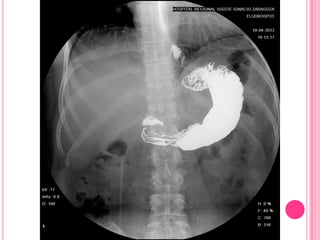

El estudio baritado muestra un esófago dilatado por alteración del peristaltismo y

falta de relajación del esfínter esofágico inferior, que presenta el típico aspecto en

"pico de flauta" (flechas)